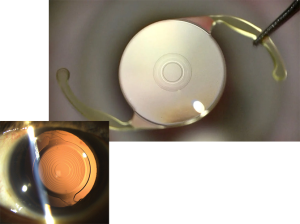

A phakic intraocular lens (IOL) is a type of lens implanted into the eye to correct vision, typically for patients with high levels of near-sightedness (myopia), farsightedness (hyperopia), or astigmatism.

Unlike traditional Intraocular Lenses, which are implanted after removing the eye’s natural lens (such as in cataract surgery), phakic IOLs are placed in the eye without removing the natural lens.

There are a number of types of Phakic IOLs but their general key purpose is to correct refractive errors in patients who are not good candidates for other laser vision correction procedures like LASIK or PRK, often due to having very thin corneas or severe refractive errors.